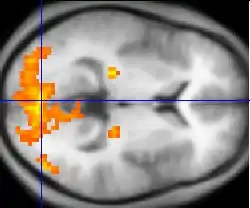

Нейровизуализация с помощью аппаратуры фМРТ и ПЭТ работы мозга при шизофрении указывает на функциональные отличия, затрагивающие чаще всего фронтальные и височные доли, а также гиппокамп[137]. Эти отличия связывают с нейрокогнитивными нарушениями, часто отмечаемыми при шизофрении[138], однако трудно отделить возможный вклад в эти нарушения, связанный с антипсихотическими препаратами, которыми лечились почти все пациенты, принимавшие участие в исследованиях[139]. У больных шизофренией также обнаруживается гипофронтальность — уменьшение притока крови к префронтальным и лобным отделам коры головного мозга[140][141].